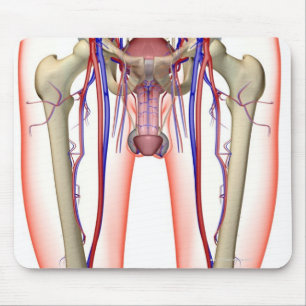

Mousepad Vértebras cervicais

PreçoR$ 77,30